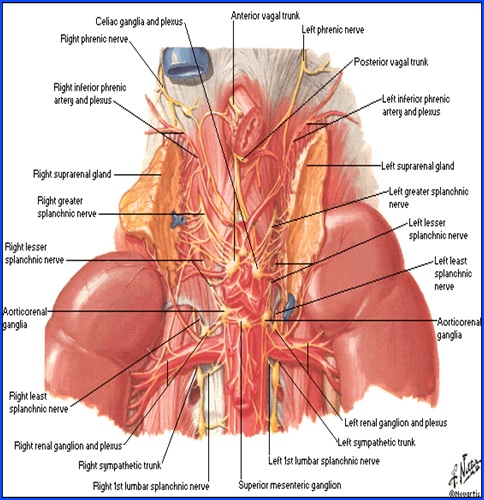

Glanda suprarenala

Anatomie

- glandă pereche situată la polul superior al rinichilor;

- formă piramidală în dreapta şi arcuată, semilunară în stânga;

- dimensiuni medii: 5/3/1 cm;

- greutatea ~ 5 g.